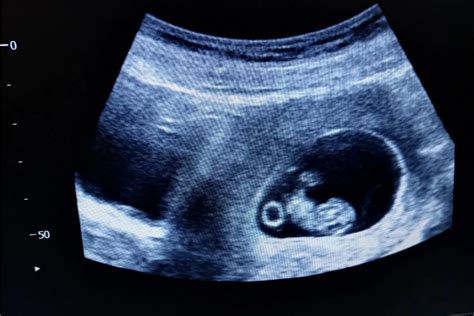

Nízko Uložené Dieťa Počas Tehotenstva: Príčiny, Riziká a Odporúčania

Vnímanie pohybov dieťaťa je jedným z najvzrušujúcejších momentov v tehotenstve. Tieto pohyby sú nielen prejavom života, ale aj dôležitým indikátorom zdravia a pohody dieťaťa. Avšak, keď žena začne cítiť pohyby nízko v podbrušku, môže to vyvolať obavy a otázky. Tento článok sa zameriava na príčiny nízko vnímaných pohybov dieťaťa, ako aj na ďalšie dôležité aspekty spojené s polohou plodu počas tehotenstva.

Prečo Cítim Pohyby Nízko v Podbrušku?

Pociťovanie pohybov nízko v podbrušku môže mať niekoľko príčin. Jednou z nich je poloha dieťaťa. Ak je dieťa otočené hlavičkou dole, pohyby nožičiek a ručičiek môžu byť vnímané nižšie. Ďalším faktorom môže byť poloha placenty. Ak je placenta umiestnená vpredu, na brušnej stene, môže tlmiť pohyby a žena ich môže cítiť menej intenzívne alebo v inej polohe, napríklad nízko.

V 20. týždni tehotenstva, keď žena začína pociťovať pohyby, je bežné, že ich cíti veľmi nízko, až úplne dole v podbrušku. Tento jav môže byť spojený s tým, že dieťa sa ešte úplne neusadilo v panve a jeho pohyby sú vnímané v nižšej časti maternice.